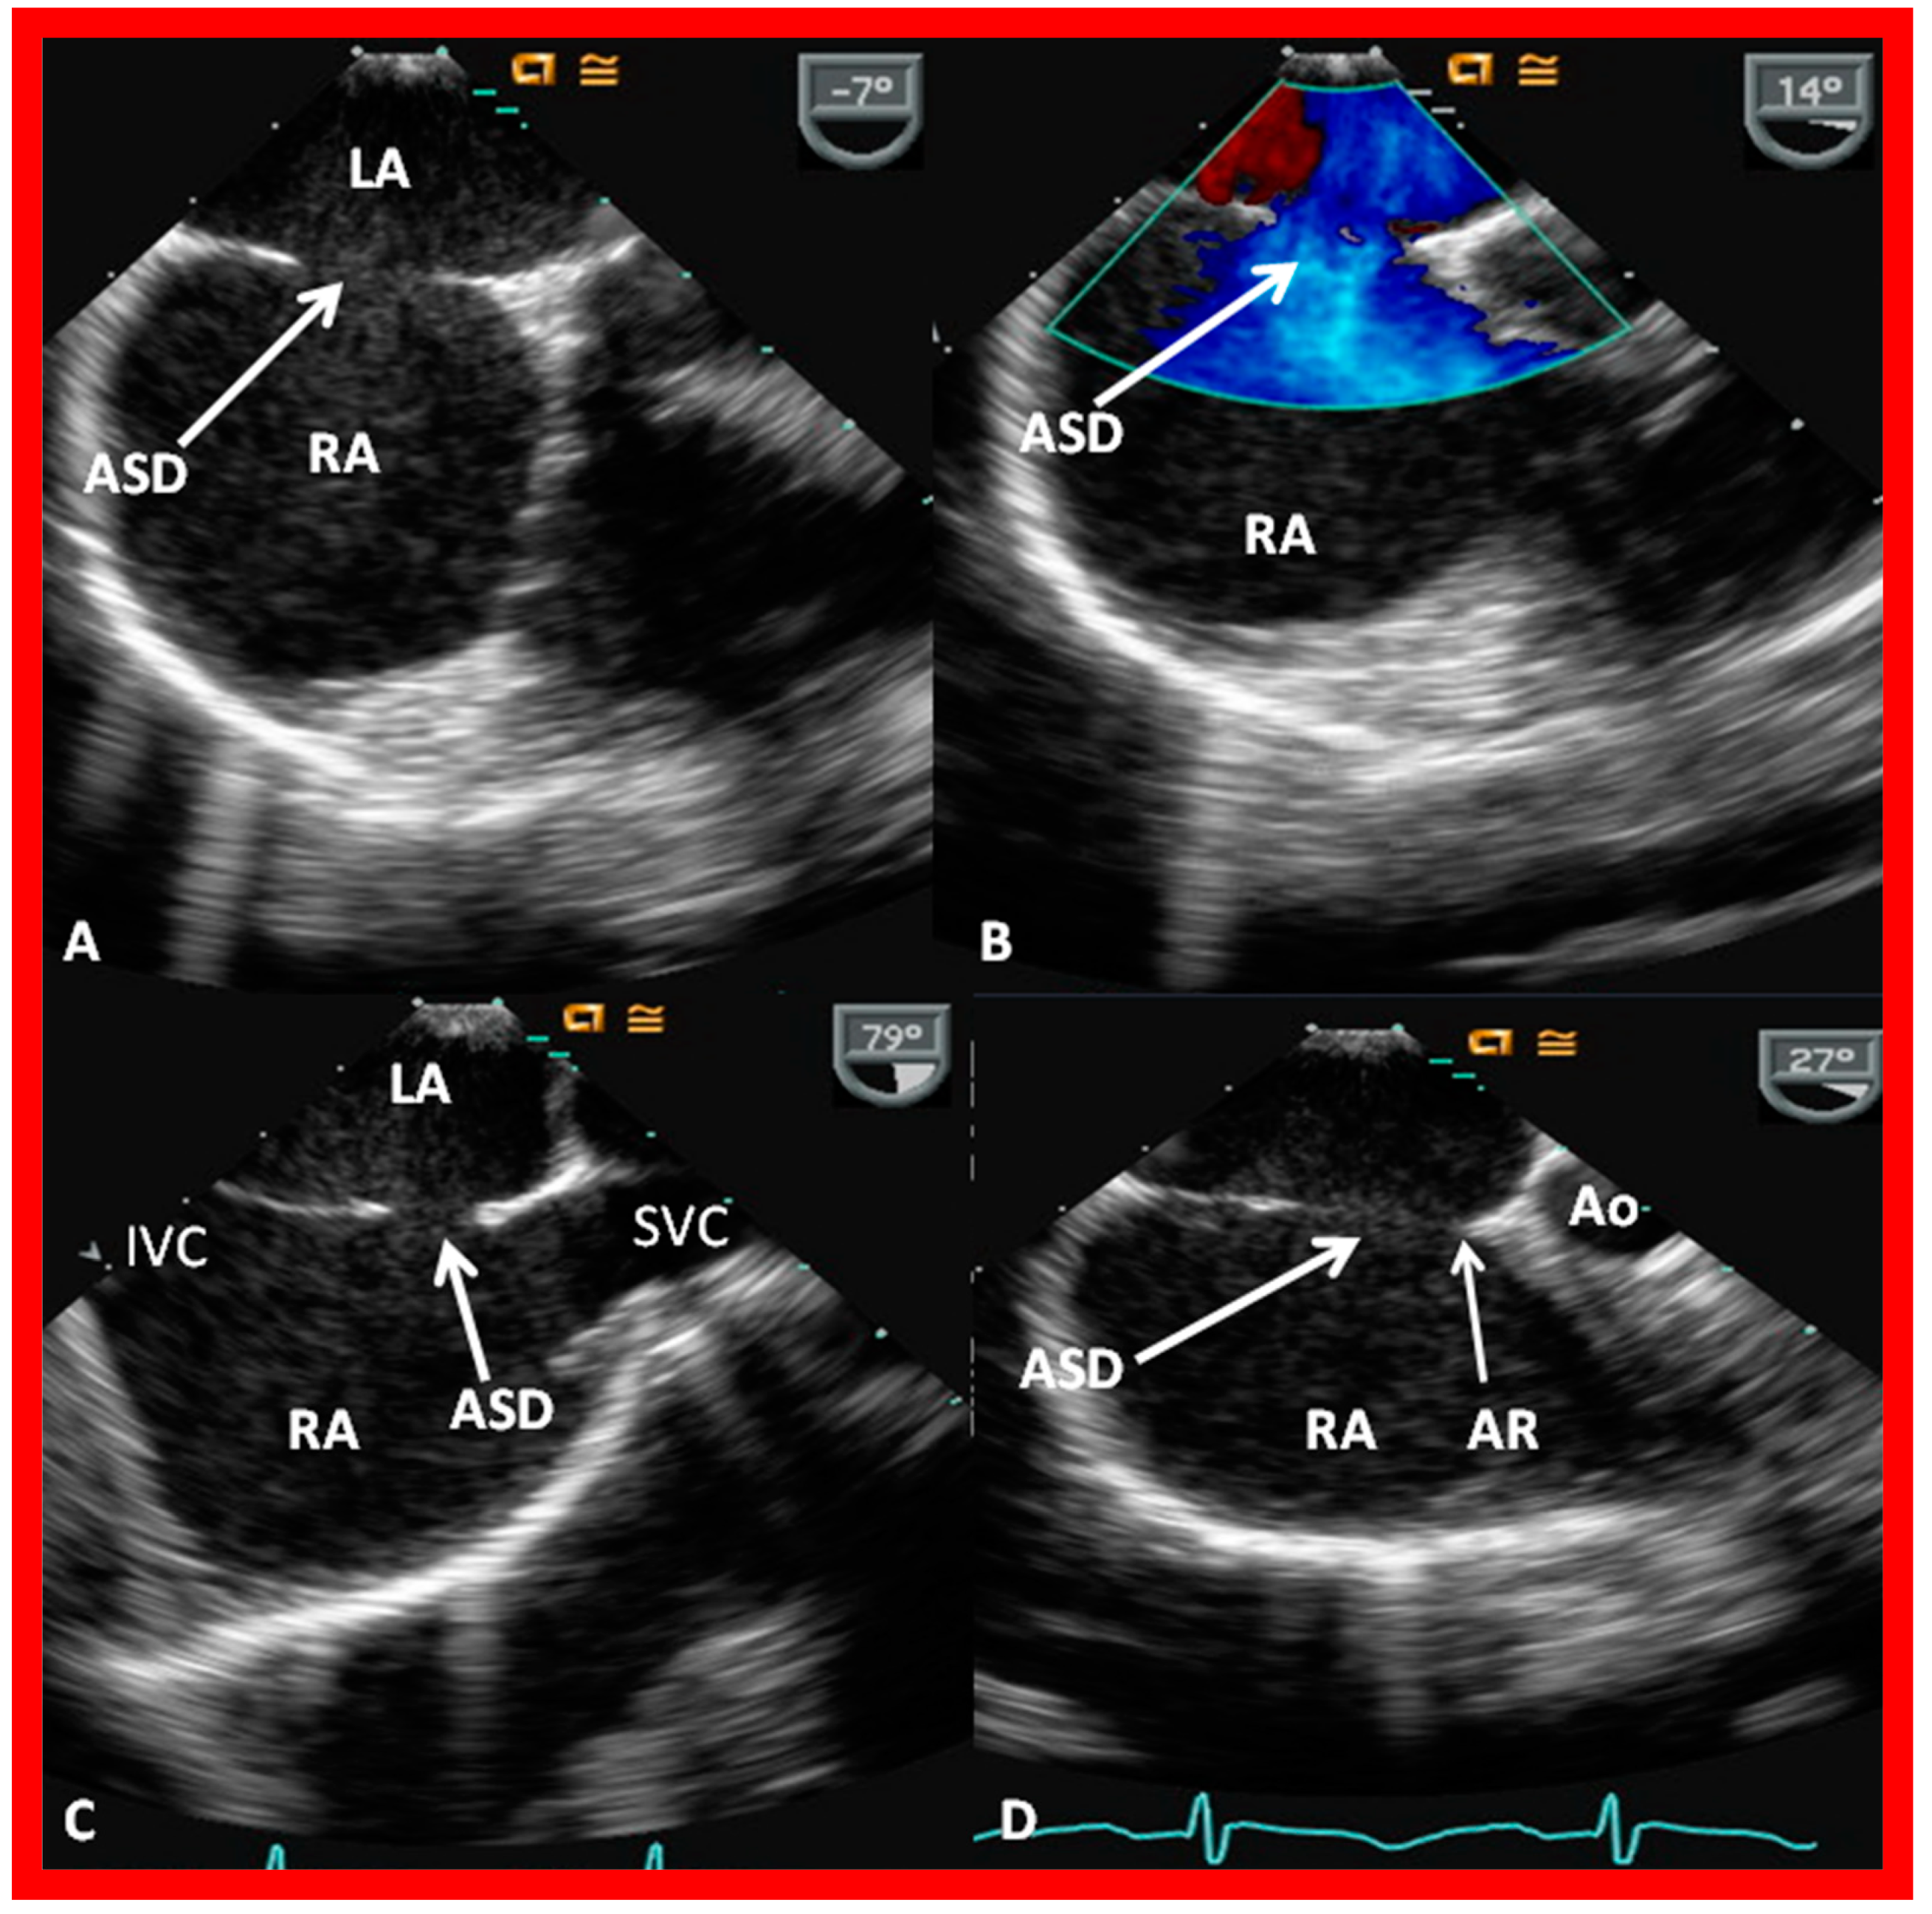

2. Diagnosis

6. TEE and ICE